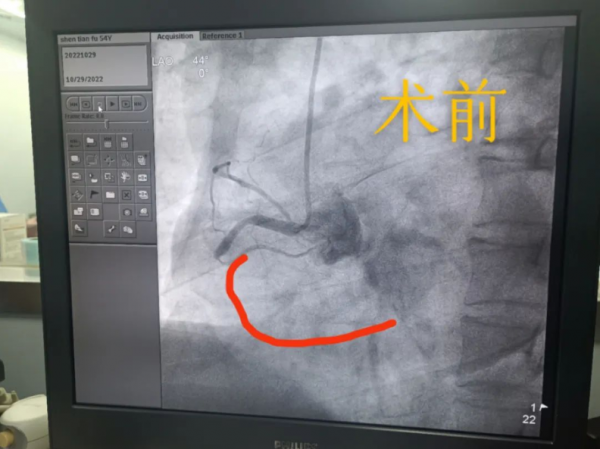

10月29日1:30,急診科的一聲“啟動胸痛中心”,田豐主任團隊,再一次投入到了生命的保衛(wèi)戰(zhàn)中。這是一位男性患者,今年54歲,身處封控區(qū)、已經出現(xiàn)急性胸痛2小時,急診科嚴格按照疫情防控的流程和要求,快速地將其轉運到院。

術前

在嚴格按照防疫的要求下,田豐主任帶領團隊馬上進行會診,根據病人的癥狀表現(xiàn)和查體,考慮是急性心肌梗死,立刻安排急診造影,發(fā)現(xiàn)回旋支嚴重狹窄、右冠完全閉塞,隨即馬上為病人開始了介入手術。